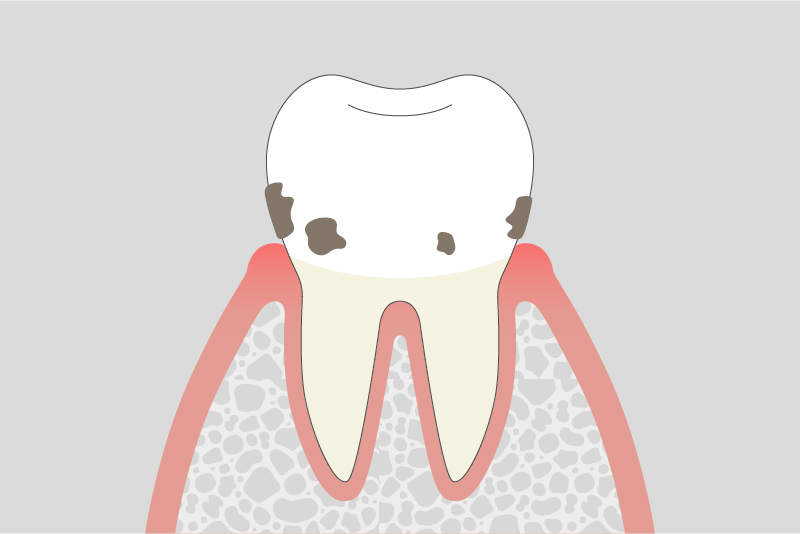

02.

軽度歯周炎

歯周ポケットが深くなり、炎症が歯ぐきの内部に広がります。腫れや出血が続くことがあり、口臭が気になる場合もあります。